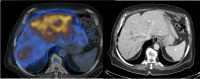

Hepatobiliary scintigraphy (HBS) has been demonstrated to predict post-hepatectomy liver failure (PHLF). However, existing cutoff values for future liver remnant function (FLR-F) were previously set according to the "50-50 criteria" PHLF definition. Methods of calculation and fields of application in liver surgery have changed in the meantime. The aim of this study was to demonstrate the role of HBS combined with single photon emission computed tomography (SPECT/CT) in predicting severity of PHLF, according to the International Study Group of Liver Surgery (ISGLS). All patients submitted to major hepatectomy with preoperative HBS-SPECT/CT between November 2016 and December 2019, were analyzed. Patients were resected according to hepatic volumetry. Receiver operating characteristic (ROC) curve analysis was performed to identify cutoffs of FLR function for predicting PHLF according to ISGLS definition and grading. Of the 38 patients enrolled, 26 were submitted to one-stage hepatectomy (living liver donors = 4) and 12 to two-stage procedures (portal vein embolization = 4, ALPPS = 8). Overall, 18 patients developed PHLF according to ISGLS criteria: 12 of grade A (no change in the patient's clinical management) and 6 of grade B (change in clinical management). ROC analysis established increasingly higher cutoffs of FLR-F for predicting PHLF according to the "50-50 criteria", ISGLS grade B and ISGLS grade A/B, respectively. HBS with SPECT/CT may help to assess severity of PHLF following major hepatectomy. Prospective multicenter trials are needed to confirm the effective role of HBS-SPECT/CT in liver surgery.